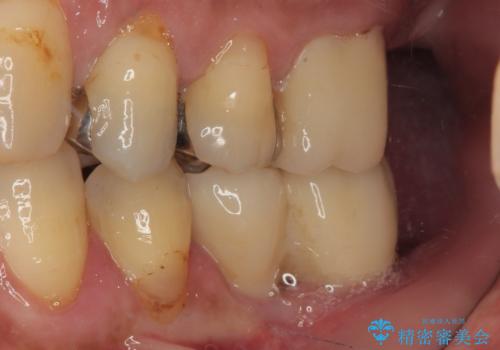

- 連結されている奥歯がグラグラしていて、インプラント治療を希望して来院された患者様です。

連結の手前の歯は歯根が破折して、クラウンが歯から外れており、奥の歯は動揺により歯根周辺の骨が吸収している状態でした。